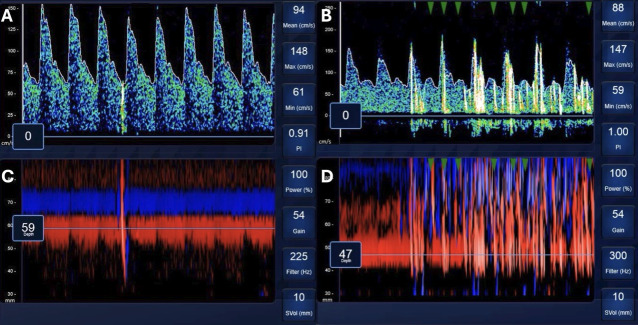

背景:我们之前使用经颅多普勒(TCD)证实了COVID-19肺炎患者中经肺泡传输(TPBT)的高患病率,但这些观察结果需要证实。方法:对两家学术医疗中心因COVID-19肺炎住院并需要任何形式呼吸支持的患者进行研究。第一次TCD研究在入组时进行,如果参与者仍住院,则在大约7天和14天后重复进行。结果:91名受试者入组。第一次TCD时,14例(15%)患者接受鼻插管供氧,41例(45%)患者接受高流量鼻插管供氧,8例(9%)患者接受无创正压,28例(31%)患者接受机械通气,2例(2%)患者接受体外膜氧合。33名参与者(36%)在第一次TCD时表现出TPBT。有证据表明,TPBT和心率增加与院内死亡相关(p=0.02)。心率每增加一个单位,TPBT患者的死亡几率增加11% (OR 1.11, 95% CI 1.02 ~ 1.20, p=0.01);然而,没有证据表明没有TPBT的患者有这种增加(OR 1.01, 95% CI 0.97 ~ 1.05, p=0.76)。在随后的TCD评估中,55%的参与者在第二次TCD评估中表现出TPBT, 85%的参与者在第三次TCD评估中表现出TPBT。结论:COVID-19肺炎住院患者中TPBT的患病率高于预期,并且在存活和住院的患者中,TPBT的存在随着时间的推移而增加。在TPBT患者中,心率增加(高动力循环的标志)与死亡率增加有关。

Background: We previously demonstrated a high prevalence of transpulmonary bubble transit (TPBT) using transcranial Doppler (TCD) in patients with COVID-19 pneumonia, but these observations require confirmation.

Methods: Patients at two academic medical centres, hospitalised with COVID-19 pneumonia and requiring any form of respiratory support, were studied. The first TCD study was performed at the time of enrolment and repeated approximately 7 and 14 days later if participants remained hospitalised.

Results: 91 participants were enrolled. At the first TCD, 14 participants (15%) were receiving oxygen by nasal cannula, 41 participants (45%) were receiving oxygen by high flow nasal cannula, 8 participants (9%) were receiving non-invasive positive pressure, 28 participants (31%) were receiving mechanical ventilation and 2 participants (2%) were receiving extracorporeal membrane oxygenation. 33 participants (36%) demonstrated TPBT at the first TCD. There was evidence that the presence of TPBT and increased heart rate together was associated with in-hospital death (p=0.02). For every one-unit increase in heart rate, the odds of death increased 11% (OR 1.11, 95% CI 1.02 to 1.20, p=0.01) for those with TPBT; however, there was no evidence of this increase for those without TPBT (OR 1.01, 95% CI 0.97 to 1.05, p=0.76). For participants with subsequent TCD assessments, 55% demonstrated TPBT during the second TCD assessment, and 85% demonstrated TPBT at the third TCD assessment.

Conclusions: The prevalence of TPBT in hospitalised patients with COVID-19 pneumonia is higher than expected and the presence of TPBT increases over time in those that remained alive and hospitalised. In patients with TPBT, increased heart rate, a marker of hyperdynamic circulation, is associated with increased mortality.